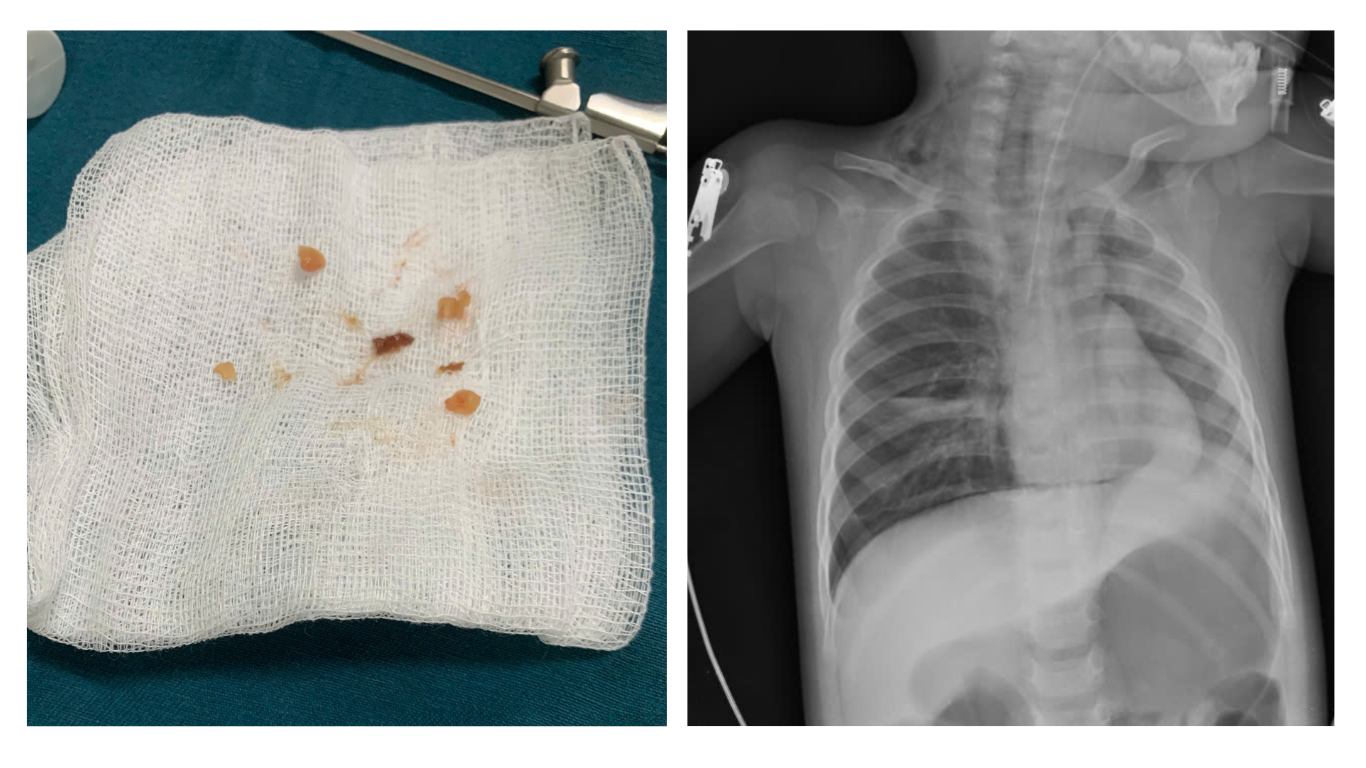

Khi được đưa vào viện, các bác sỹ đã nhanh chóng cấp cứu, lấy các dị vật, tái thông đường thở cho trẻ, tiến hành đặt nội khí quản và thở máy. Song, điều khó khăn ở đây là dưới tác động của nhiệt độ cơ thể trẻ, các mảnh kẹo tiếp tục tan ra thành mạch nha dính chặt vào các hạt lạc và gây bít tắc đường thở. Thậm chí, đã có thời điểm trẻ ngừng tim. Các hình ảnh chụp X-Quang ngực cho thấy hai bên phổi của trẻ mờ rải rác, nhất là tại vùng đỉnh và cạnh rốn phổi, góc sườn hoành hai bên nhọn.

Để cứu bệnh nhi, bệnh viện Sản Nhi Quảng Ninh đã triển khai quy trình báo động đỏ, quy trình phối hợp hội chẩn – cấp cứu liên viện giữa Bệnh viện với e-kip Bệnh viện Nhi Trung ương do BSCKII Lê Thanh Chương – Phó Giám đốc Trung tâm Hô hấp, Bệnh viện Nhi Trung ương làm trưởng nhóm đã trực tiếp có mặt phối hợp, sử dụng các dụng cụ chuyên dụng để nội soi và cẩn trọng gắp các dị vật lọt sâu trong đường thở cho trẻ. Sau thực hiệu thủ thuật, bệnh nhi được hồi sức tích cực kịp thời, hỗ trợ thở máy, lọc máu và các biên pháp chăm sóc đặc biệt, nhờ đó các chỉ số sinh tồn dần cải thiện, các chức năng, cơ quan dần ổn định bình thường và đến nay đã được ra viện.